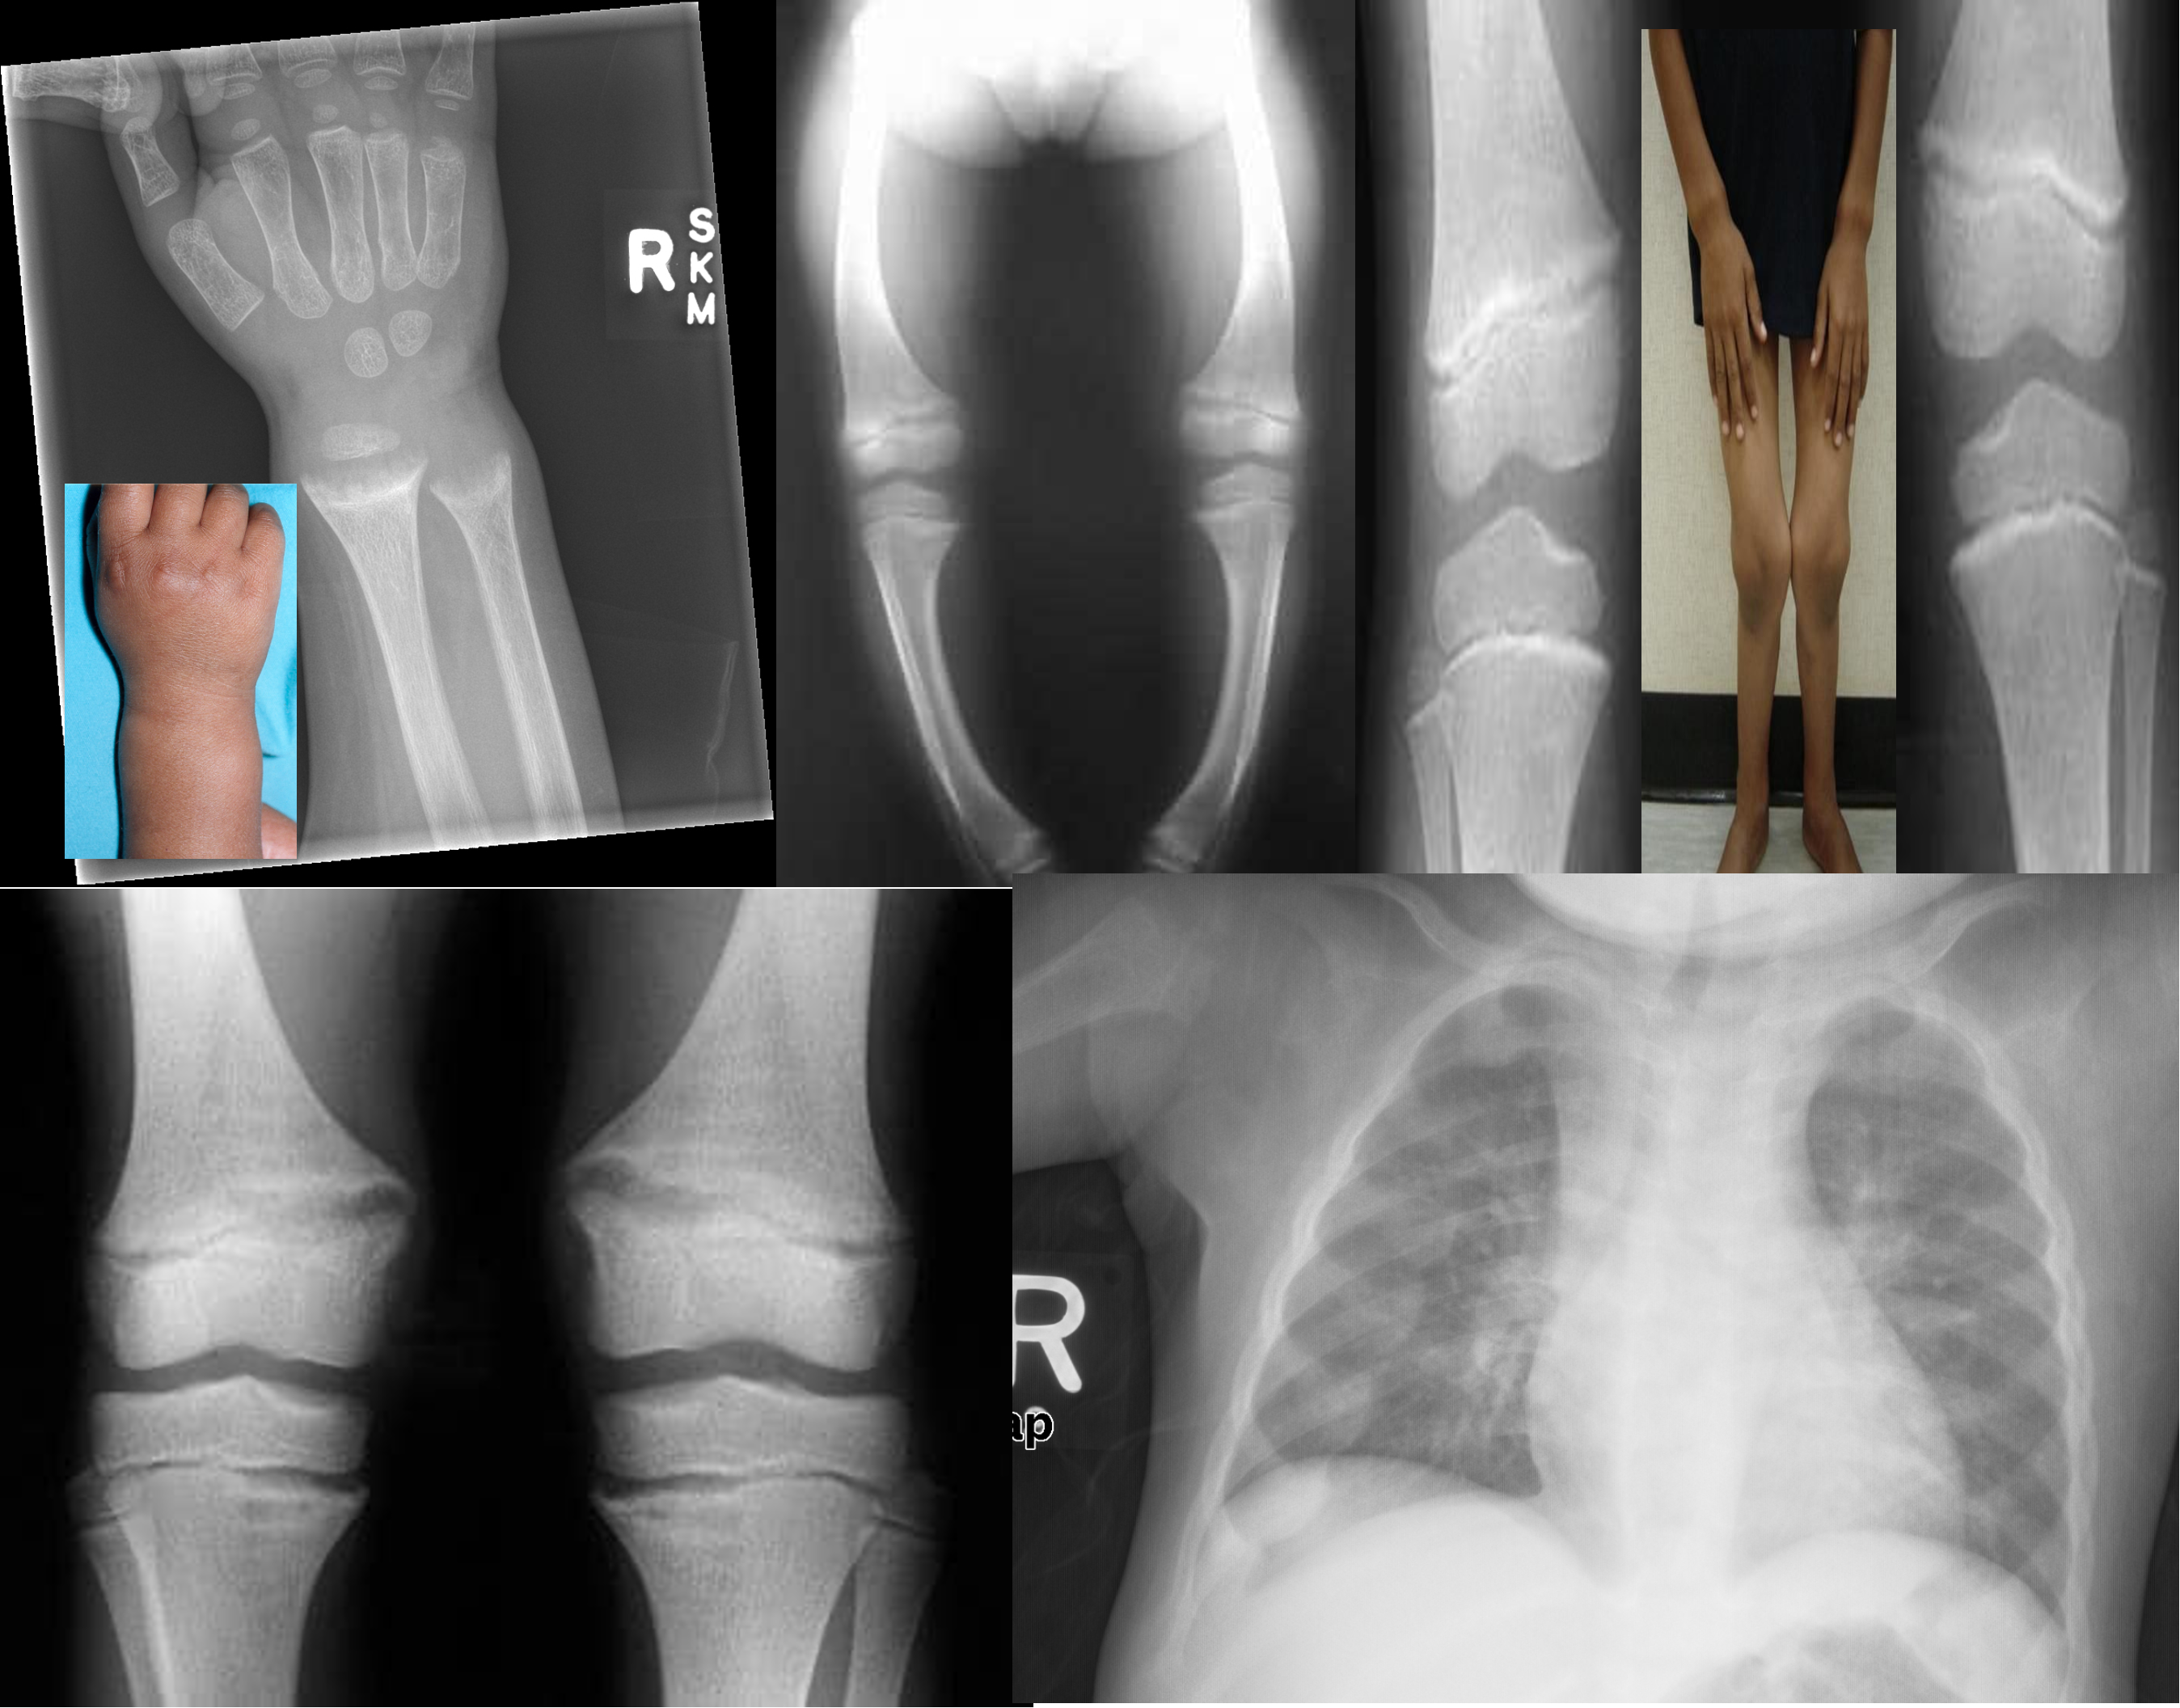

X-ray Findings

Fraying and widening of the growth plate

Cupping of the metaphysis

Bowing of the legs due to osteopenia (Genu varus)

Knock-knees (Genu Valgum)

Multiple growth arrest lines

Underdevelopment of the medial aspect of both the tibial plateau and the femoral condyle

Rachitic rosary (differential for child abuse also seen in proximal)

- X-ray of left wrist and/or knees